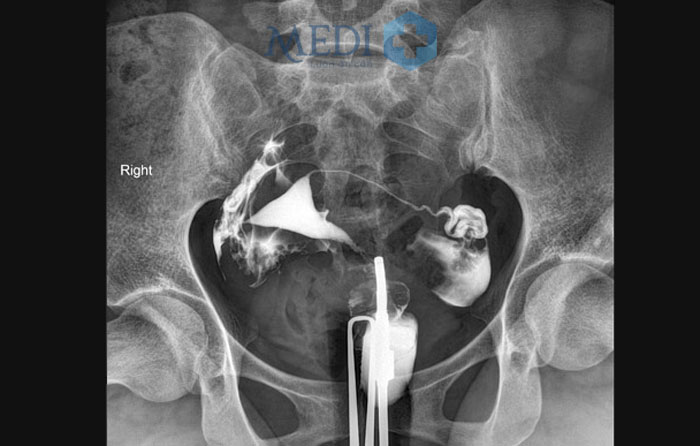

Khi chụp X-Quang tử cung buồng trứng, bác sĩ sẽ bơm chất cản quang vào trong tử cung và ống dẫn trứng. Một dạng chất lỏng có chứa chất cản quang tan trong nước có vai trò hiện hình các cấu trúc của buồng tử cung và vòi trứng trên màn hình X-quang.

Chụp X quang tử cung vòi trứng

Hình ảnh chụp X quang buồn trử cung vòi trứng

Dựa vào hình ảnh thuốc cản quang hiển thị trên phim chụp bác sĩ nhận định kích thước, hình dạng của tử cung và ống dẫn trứng có thể phát hiện được những bất thường ở các cơ quan, bộ phận này.

• Bước 3: Sau khi bơm thuốc cản quang, các bác sĩ sẽ tiến hành chụp để đánh giá thuốc trong buồng tử cung và vòi trứng hai bên, sau khoảng 15 phút tiến hành chụp thì thoát thuốc để xem thuốc cản quang có thoát vào khoang phúc mạc thông qua vòi trứng hai bên từ đó đưa ra kết luận về tình trạng bệnh lý của buồng tử cung và sự lưu thông của vòi trứng hai bên.